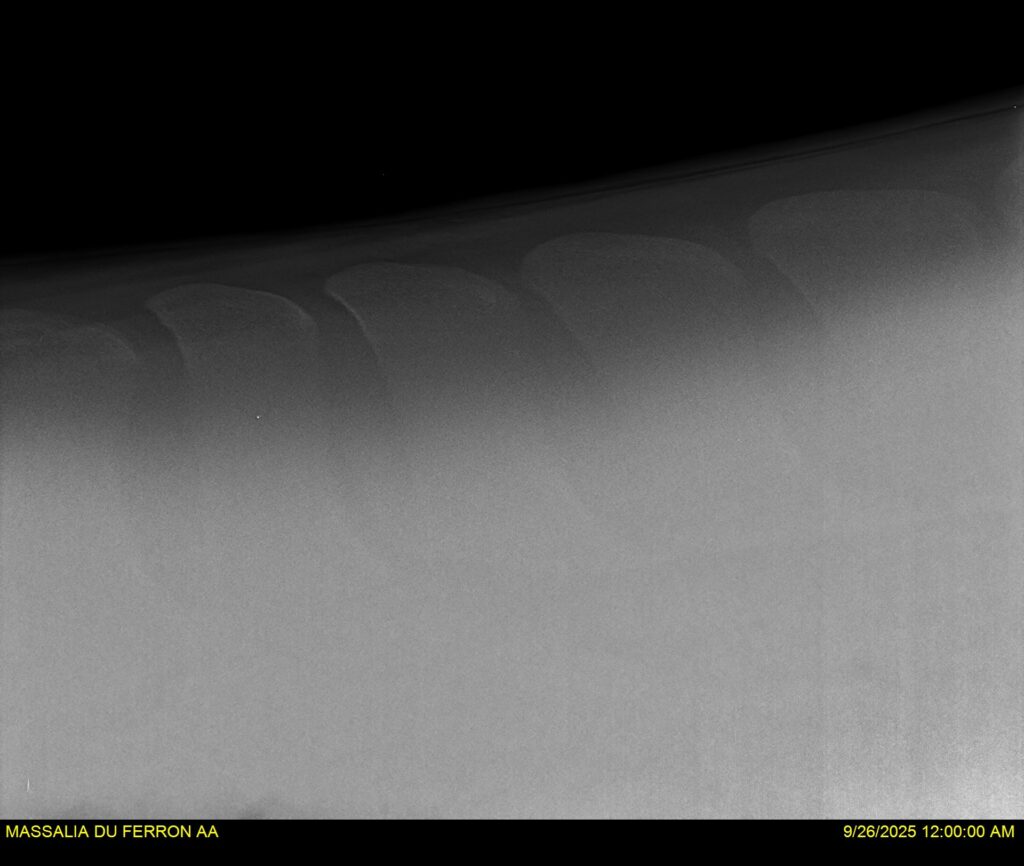

MASSALIA DU FERRON, jument qui prendra 4 ans par PRESTIGE KALONE x TRESOR DU RENOM. Un mental en or et un véritable sens de la barre ! Facile d’accès ! Bonne énergie et bons moyens. Souche moderne et très intéressante. Transport OK, maréchalerie OK, santé RAS, Bilan clichés radios OK.

RADIOS et COMPTE RENDU